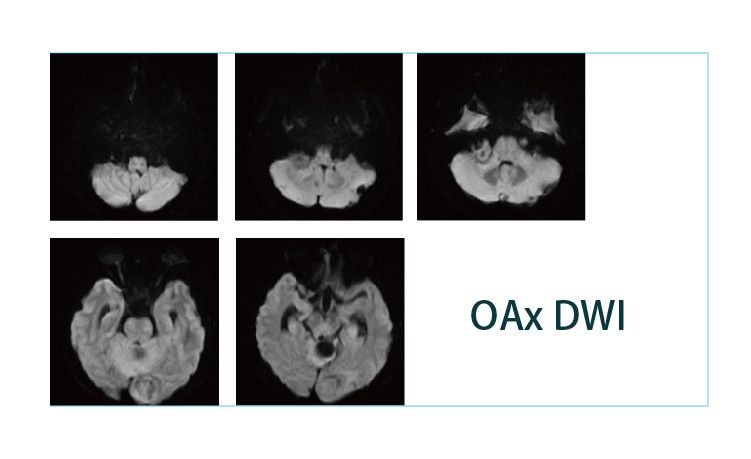

【朗润影像档案】磁共振影像病例分享(编号20190426)

【朗润影像档案】磁共振影像病例分享(编号20190419)

【朗润影像档案】磁共振影像病例分享(编号20190412)

【朗润影像档案】磁共振影像病例分享(编号20190405)